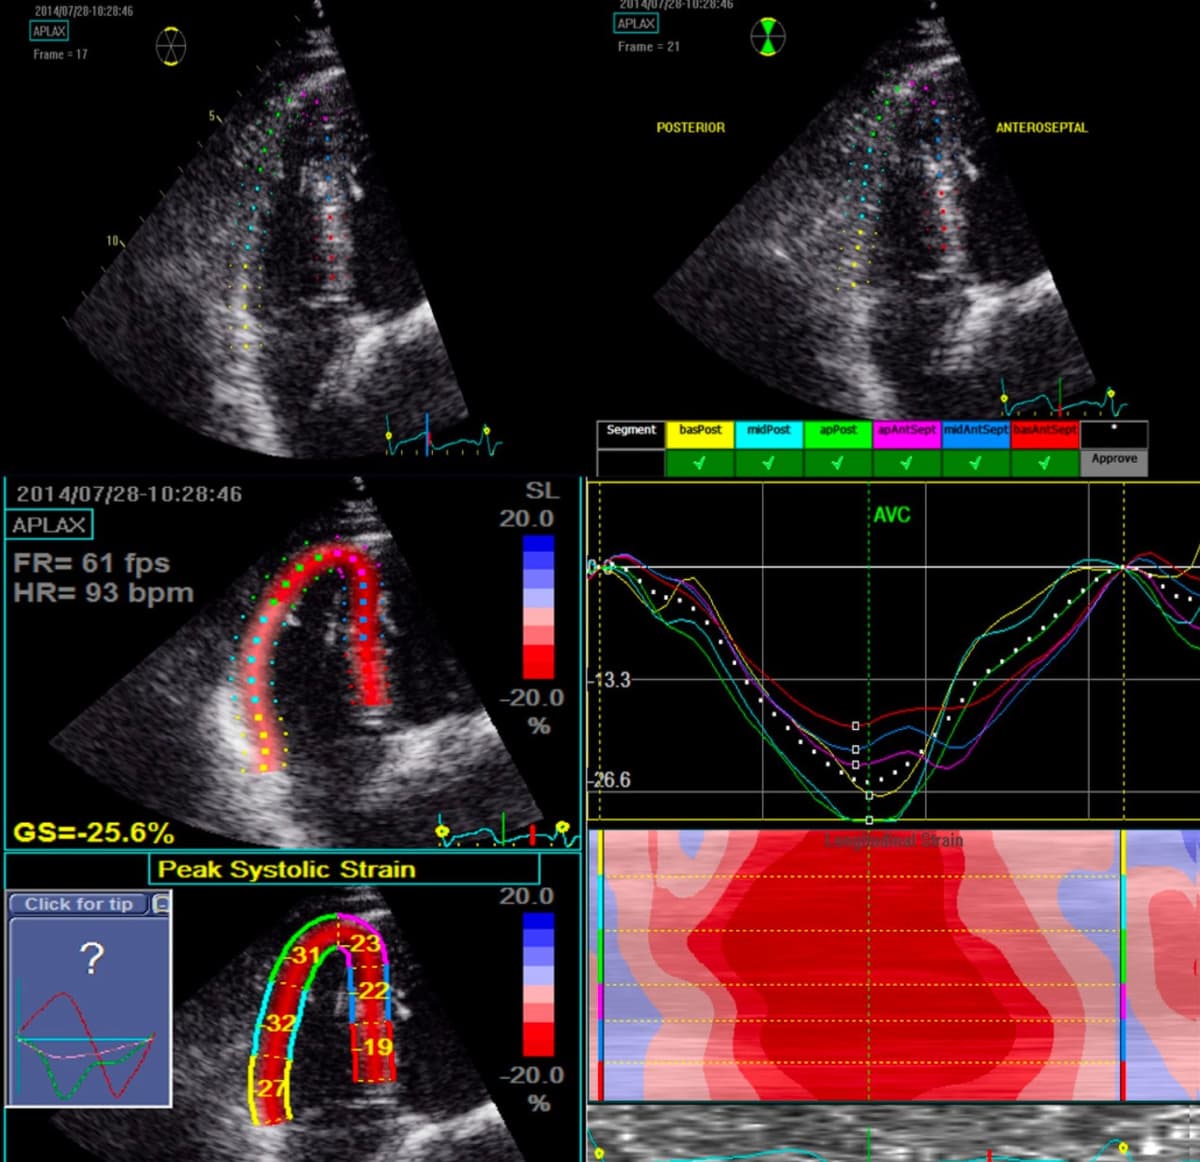

- Echocardiogram